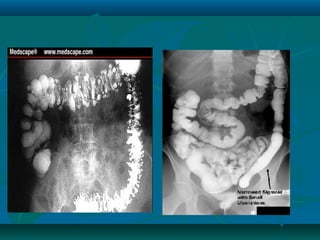

Radiology

Plain ABD. X-ray:

•Intestinal obstruction or displacement of

bowel loops by a mass.

Ultrasound:

•Thickened small bowel loops and

mesentery or abscess

Barium follow through:

•Asymmetrical alteration mucosal pattern

with narrowing or stricturing.

•Skip lesions

•Extent of the disease can be judge by air

distribution in the colon and the presence

of colonic dialatation

•Thickening of colonic wall and presence

of free fluid in abdominal cavity

•Fine mucosal granularity

•Mucosa become thickenned and

superficial ulcers are seen (collar-button

ulcers)

•Loss of haustration

Cont…..

CD

UC

Instant Barium enema

•Patchy sup. Ulceration to wide spread

deep (rose thorn ulcer)

•Cobble stone appearance and narrowing

•Superficial ulcers

•Shortened and narrowed colon in long

standing disease